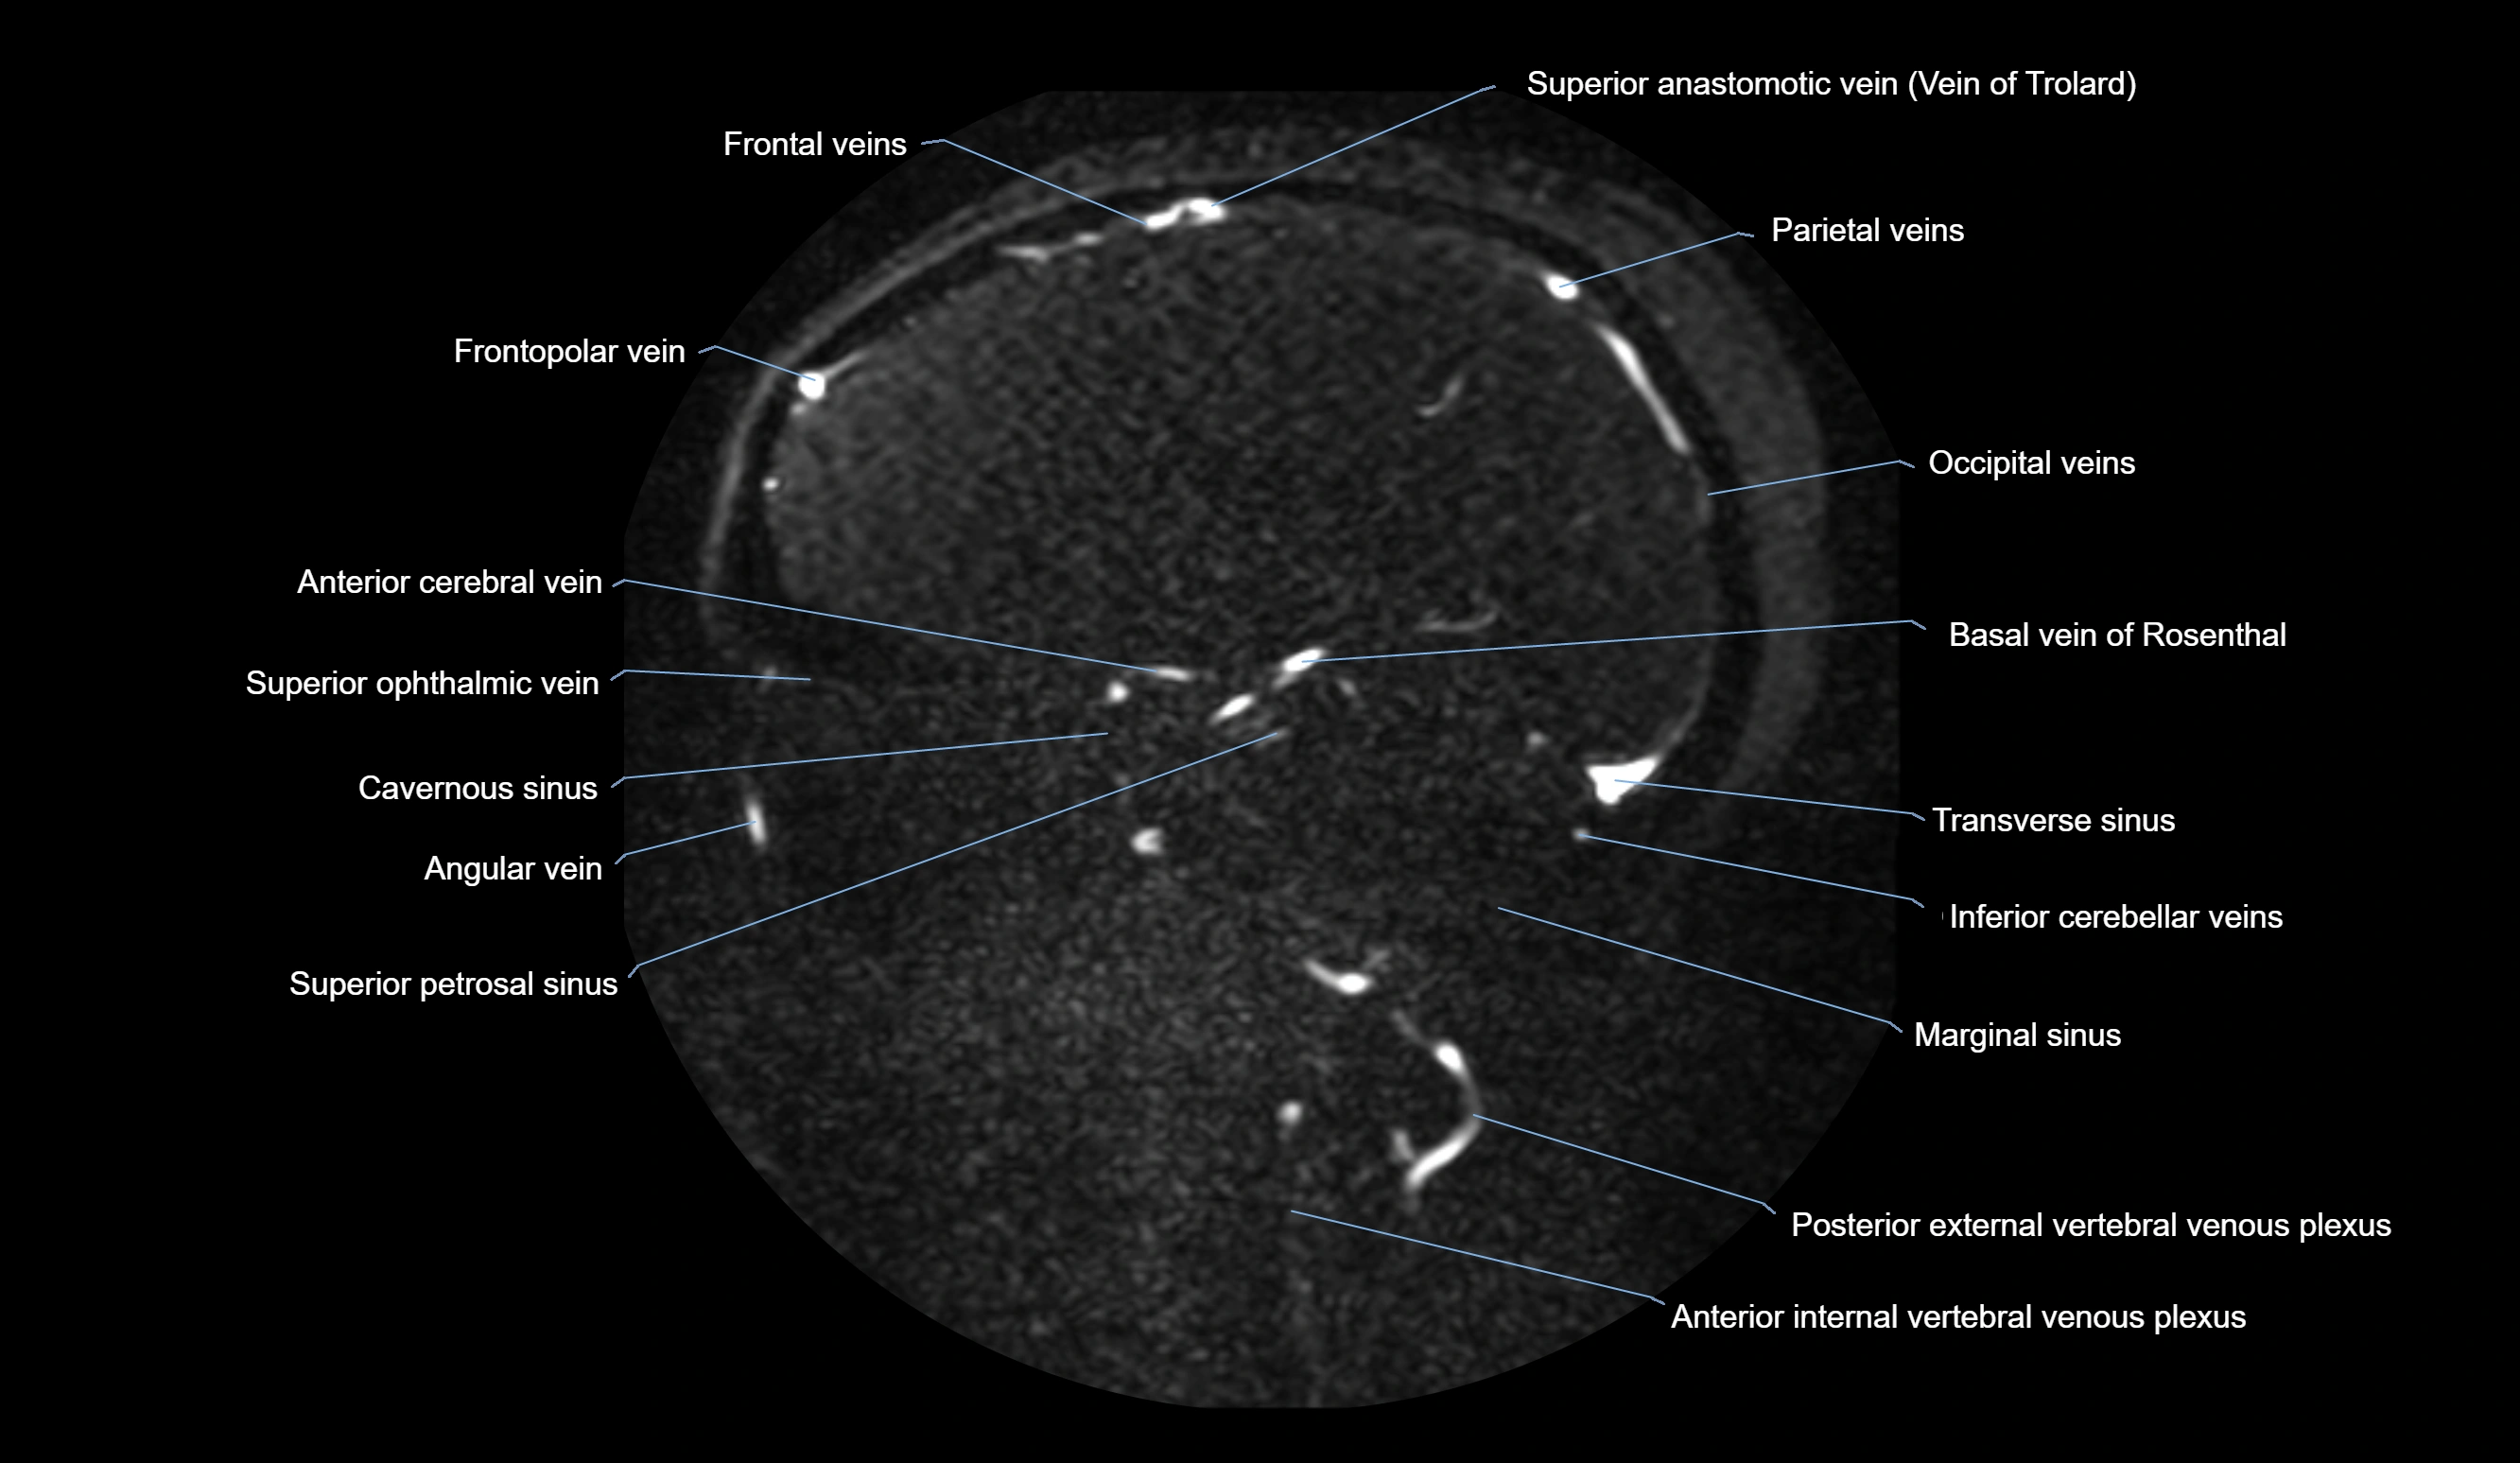

MRI Appearance

MR Venography (MRV):

• Time-of-flight (TOF) or contrast-enhanced MRV shows the angular vein as a bright enhancing venous channel

• Clearly demonstrates its continuity with the facial vein and superior ophthalmic vein

• MRV is highly useful in evaluating thrombosis, venous obstruction, or collateral venous drainage

T1 Post-Contrast (Gadolinium-enhanced MRI):

• The vein lumen enhances intensely with contrast

• Helps confirm patency or thrombus, and outlines venous communications to orbital and cavernous sinus pathways

MRI images

image